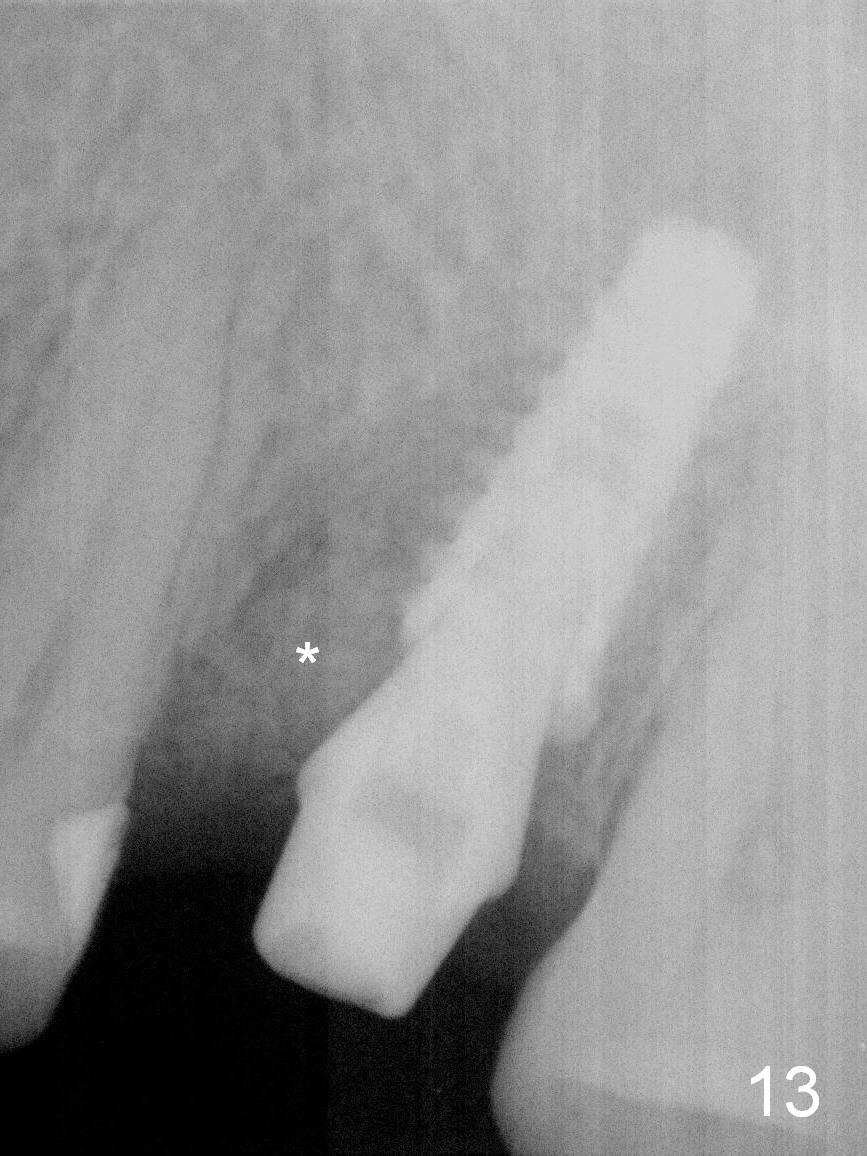

It seems that the provisional traps food. The former has been removed by the patient by the time she returns 3.5 months postop. The gingiva around the implant is healthy. The organization of the bone graft has changed (Fig.13, as compared to Fig.8,9). The implant has osteointegrated. Take photos to show the buccal and palatal gingival margin before impression. In fact the newly formed gingiva covers the margin of the abutment 5 months postop (Fig.14). Laser gingivectomy is performed prior to impression. Provisional should be kept in place with good oral hygiene. The crown dislodges 8 months post cementation, probably due to bruxism, small, short abutment and open margin (Fig.15 (taken after recementation; the residual cement is removed later)).